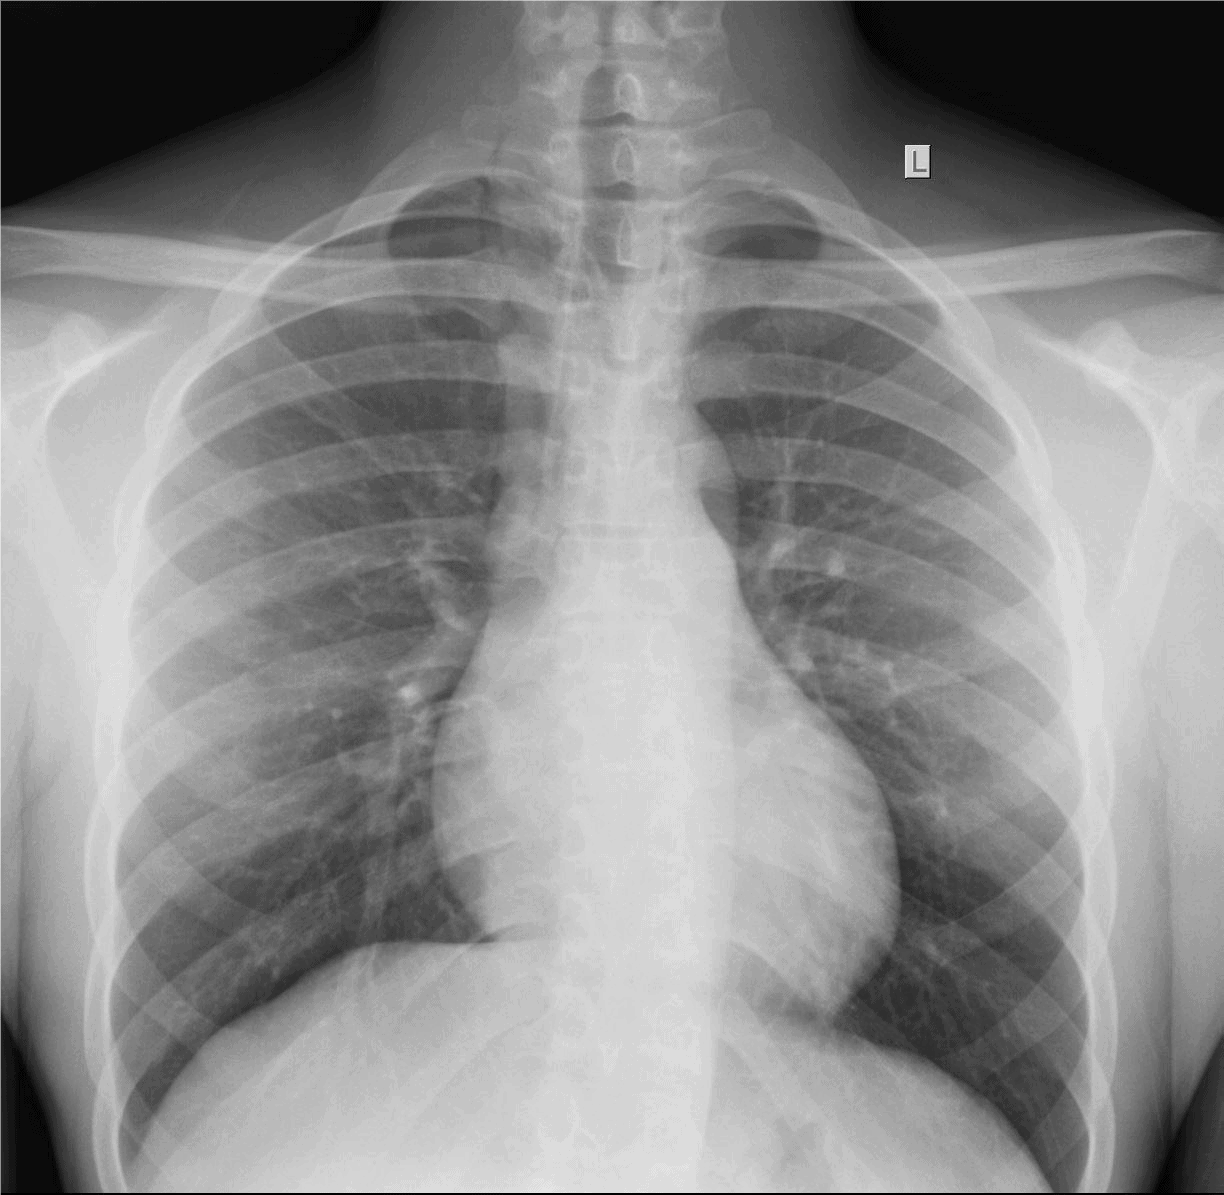

The patient is a 9-year-old girl who is brought in by her parents shortly after choking on a chicken nugget. They are concerned because even though she stopped gagging, she complains that it feels “like there’s something stuck in there.”

View the images, ordered to rule out a lodged foreign body, and consider what the diagnosis and next steps would be. Resolution of the case is described on the next page.